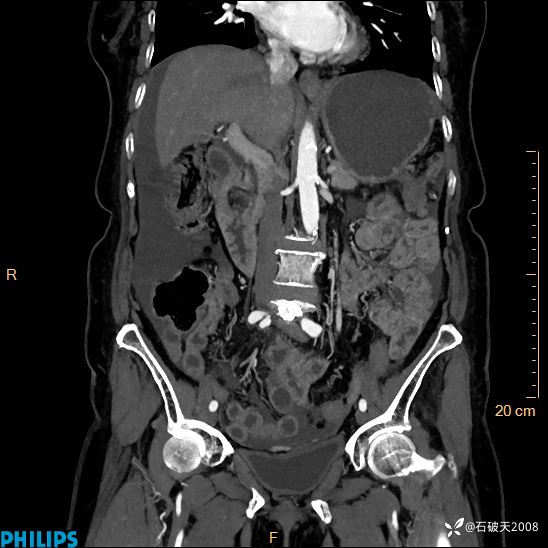

半年前住院没发现问题,近期腹痛来诊

女82岁 主 诉:腹痛半月,加重3天

平扫